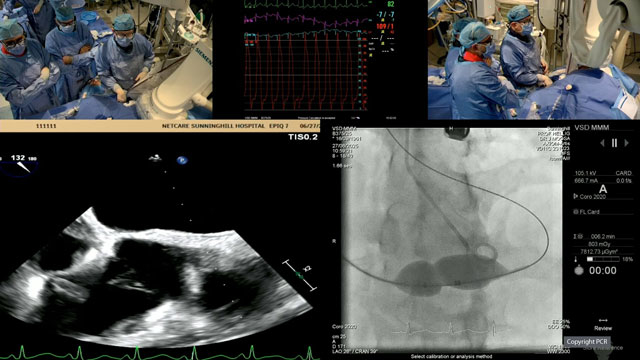

TEER for primary mitral regurgitation - LIVE case

15 May 2024 – From EuroPCR 2024

A 76-year-old male, with previous CABG in 2015, hypertension, diabetes, and pulmonary hypertension (WHO2), presented with severe symptomatic primary MR (P3 flail).

The operators implanted 1 MitraClip (XTW) step-by-step, from the transseptal puncture to the closure, guided by TEE echo and under general anaesthesia, via the venous...